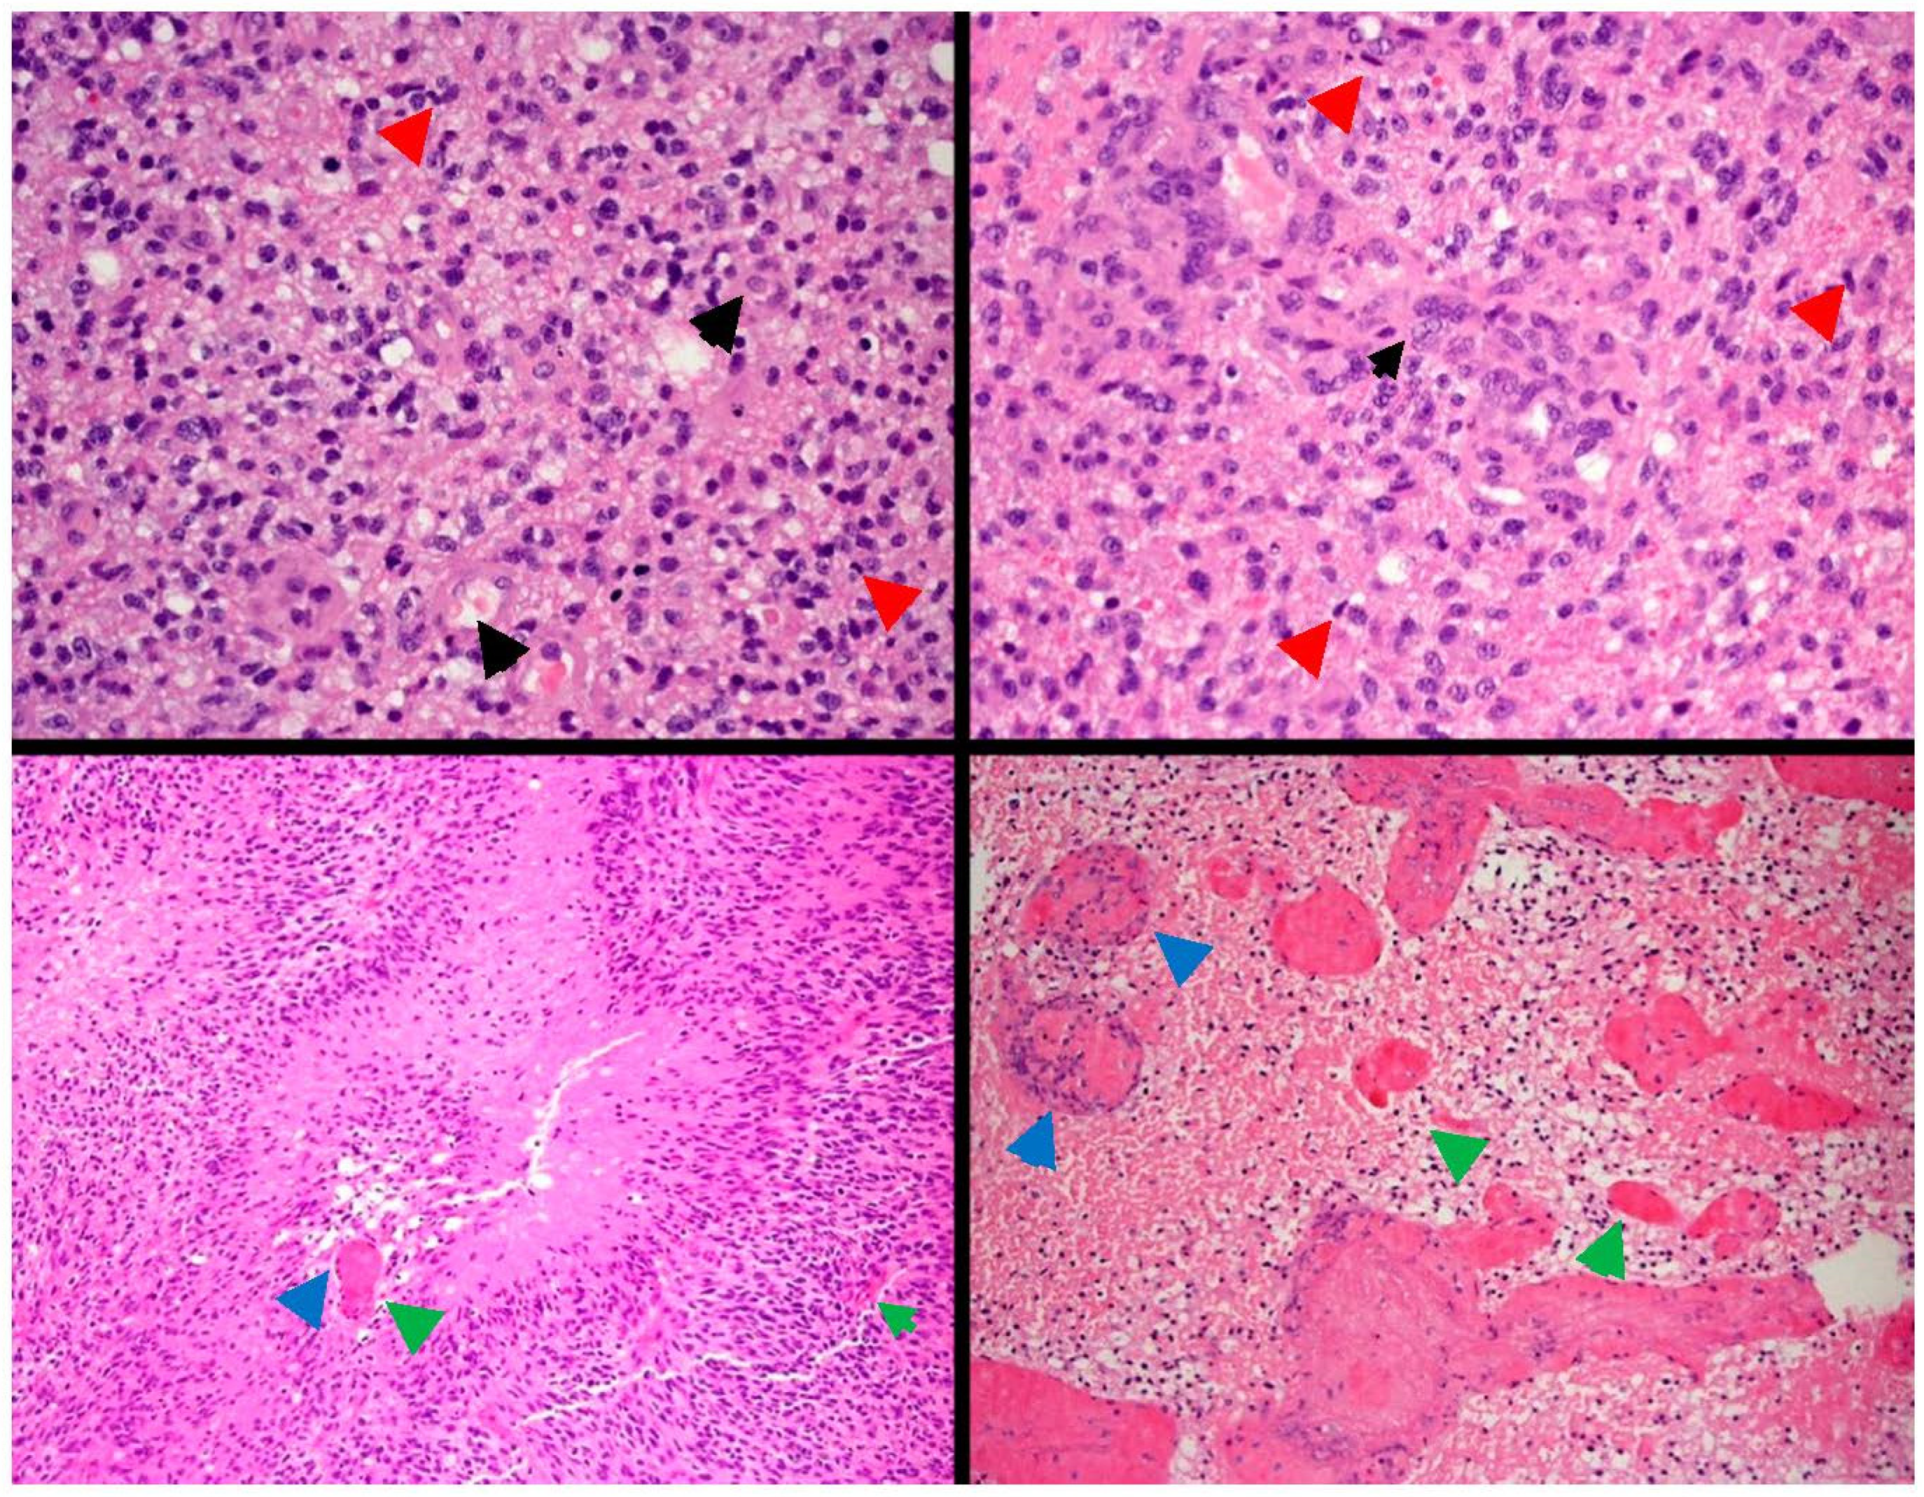

2. Glioblastoma: Origin, Histology and Classification